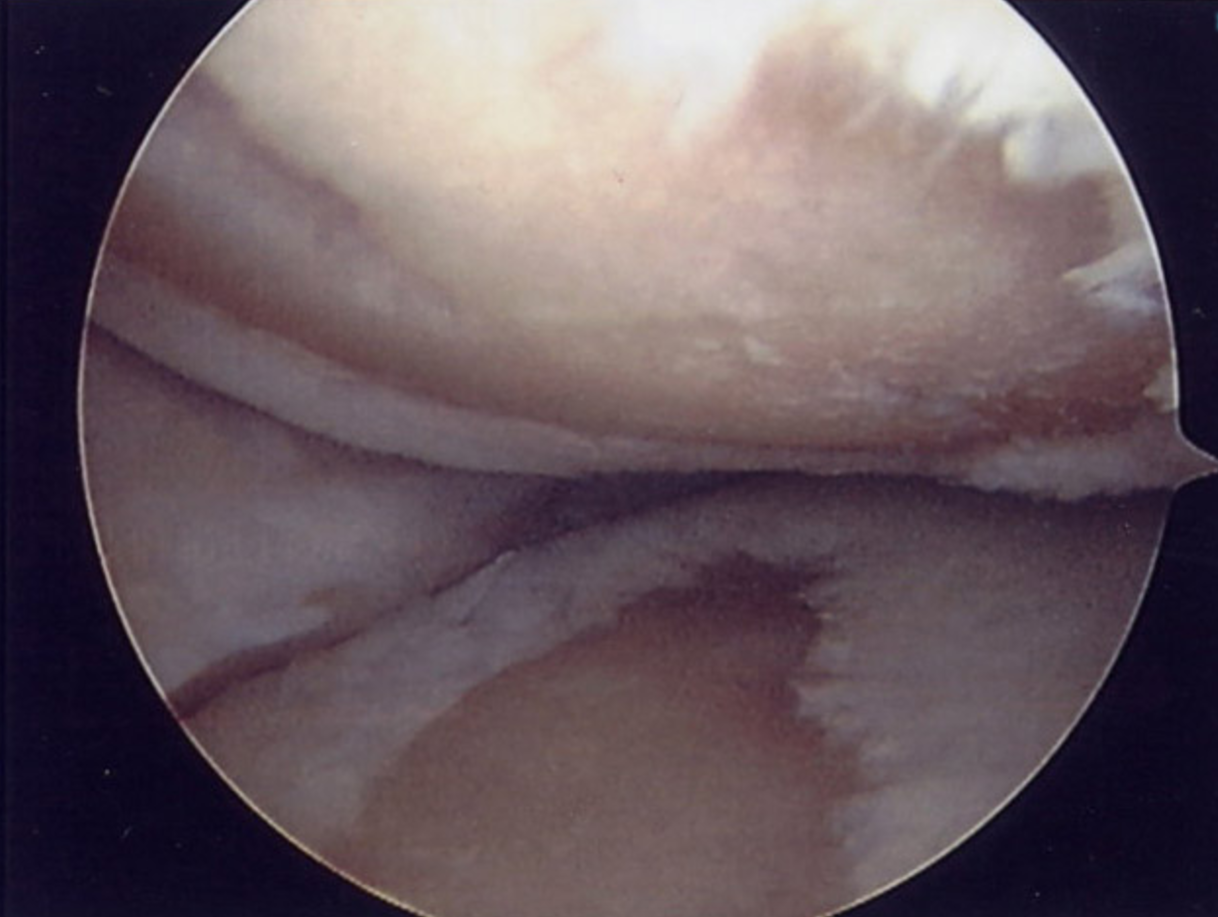

Joints are lined with a smooth layer of cartilage, which ensures their smooth movement and provides a degree of shock absorption in weight bearing joints. When a joint develops OA the cartilage is damaged and thinned. The underlying bone is also affected. In severe OA cartilage can be completely worn away resulting in bones rubbing against each other and starting to wear away. This leads to pain and instability within the joint itself. Bone reacts to compensate by the formation of bony spurs called osteophytes. These may be a further source of pain.

Most people with osteoarthritis will not require surgery. However, osteoarthritis of a joint can become so severe that the symptoms are not controlled by conservative measures. Sometimes keyhole (arthroscopic) surgery can help. For example keyhole surgery can be useful in the knee joint, for the following purposes:

To assess the severity of arthritis, and suitability of the knee joint for further procedures including high tibial osteotomy or partial knee replacement

To shave away any loose edges, or flaps of cartilage which are catching, if the history and examination findings suggest that this is taking place.